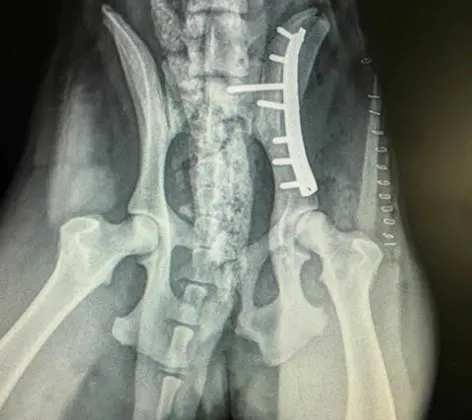

Fracture Repair

Kingsburg Veterinary Clinic is proud to offer comprehensive fracture repair for cats and dogs. Fractures (broken bones) are common in pets. Animals can break bones from trauma by being hit by cars, falling and being stepped on.

Bone Plating

Bone plating is one of the strongest and most effective methods of fixing a fracture. Fractures are common in pets and are caused by a variety of reasons.